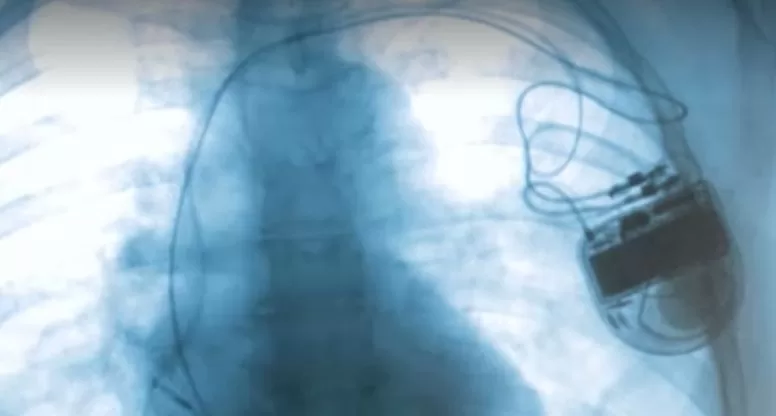

Femeii de 74 de ani îi fusese implantat un cardiostimulator în luna august, anul trecut.

Anchetatorii susțin că fost implantate, astfel, 238 de dispozitive extrase de la cadavre sau a căror sursă de proveniență nu se cunoaște. Dispozitivele au fost reutilizate, deși acest lucru este interzis de legislație și este consemnat și pe ambalaj.